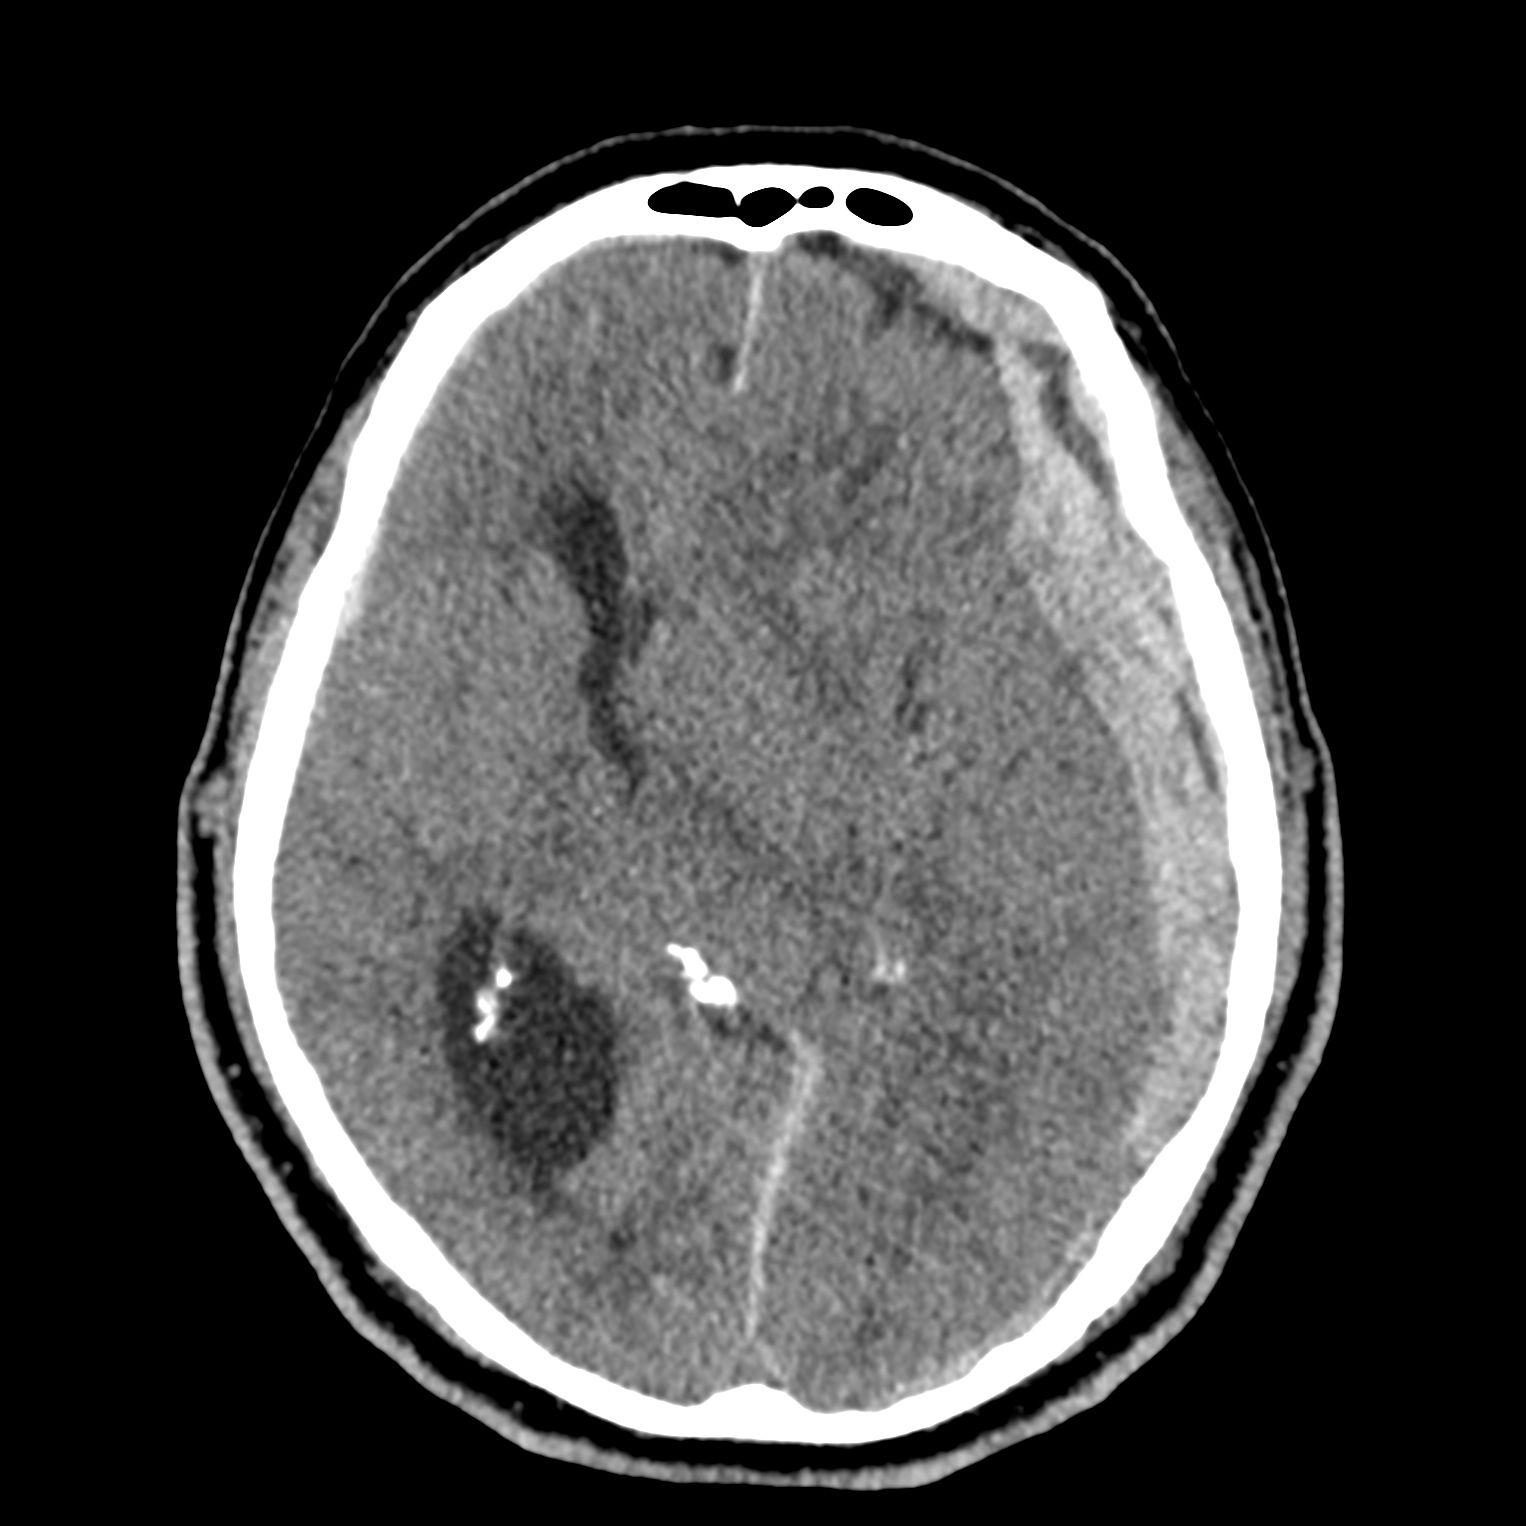

ちなみに画像診断とは、CTやMRIなどの画像を見て、正常か異常か、異常であればそれが何なのかを診断する仕事です。

Case courtesy of Andrew Dixon, Radiopaedia.org. From the case rID: 32383

医療従事者でなければ何のメリットも無いかもしれないのですが、実際の画像を自分でスクロールしながら学ぶことができるというのは、ものすごく大きなことだと思います。

さらに症例の解説を付け加えたら、読影能力アップのための強力なツールになるのではないかと期待しています。